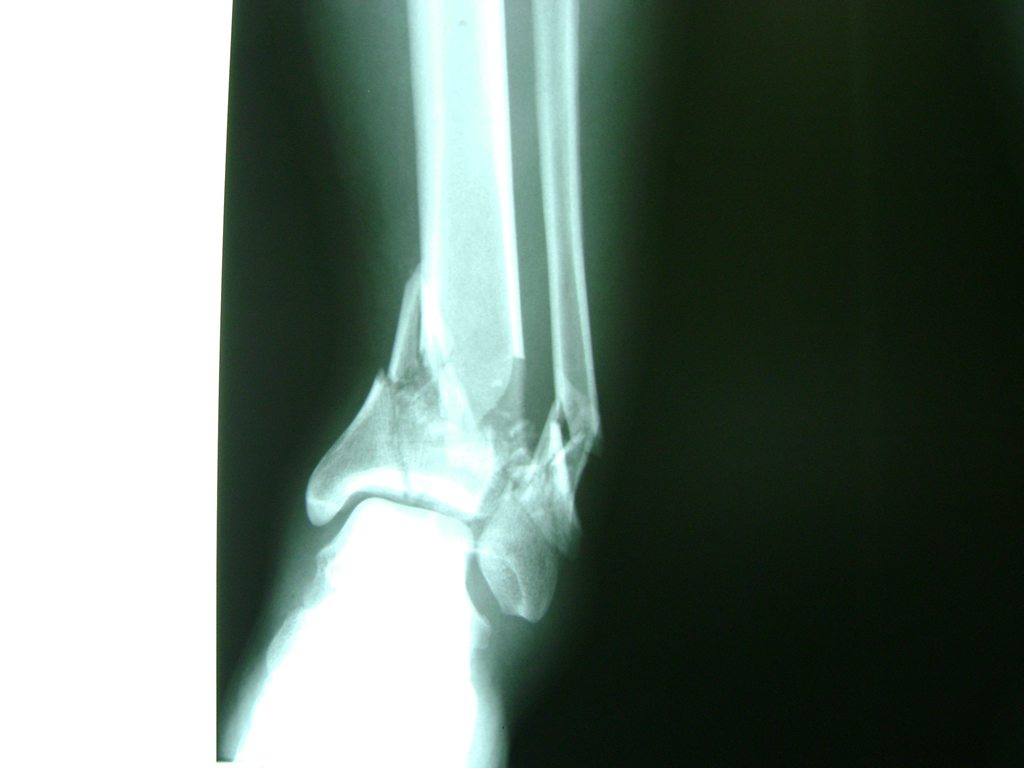

Algunas fracturas de tobillo pueden requerir cirugía si:

- Los extremos de los huesos están desalineados entre sí (desplazados).

- La fractura se extiende hasta la articulación del tobillo (fractura intra-articular).

- Los tendones o ligamentos (tejidos que sujetan los músculos y los huesos entre sí) están rotos.

- El médico cree que sus huesos probablemente no sanen apropiadamente sin cirugía.

- El médico considera que la cirugía puede permitirle una recuperación más rápida y confiable.

- En los niños, la fractura involucra la parte del hueso del tobillo donde el hueso está creciendo.